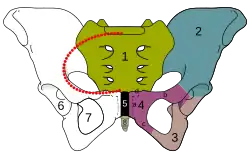

Região pélvica

Na região pélvica, os vasos sanguíneos e linfáticos aumentam de tamanho e desenvolvem novas ramificações de modo a suportar o aumento de fluxo de sangue ao útero e restante órgãos. À medida que a gravidez avança, os músculos, ligamentos e outros tecidos da região tornam-se gradualmente mais pronunciados, elásticos e fortes de modo a permitir que o útero cresça para além da pélvis e que o bebé possa atravessar o canal de parto com maior facilidade. Os ossos pélvicos sofrem poucas alterações durante a gravidez. No entanto, a hormona relaxina relaxa a união entre os ossos frontais da bacia e entre a bacia e o sacro.[1]